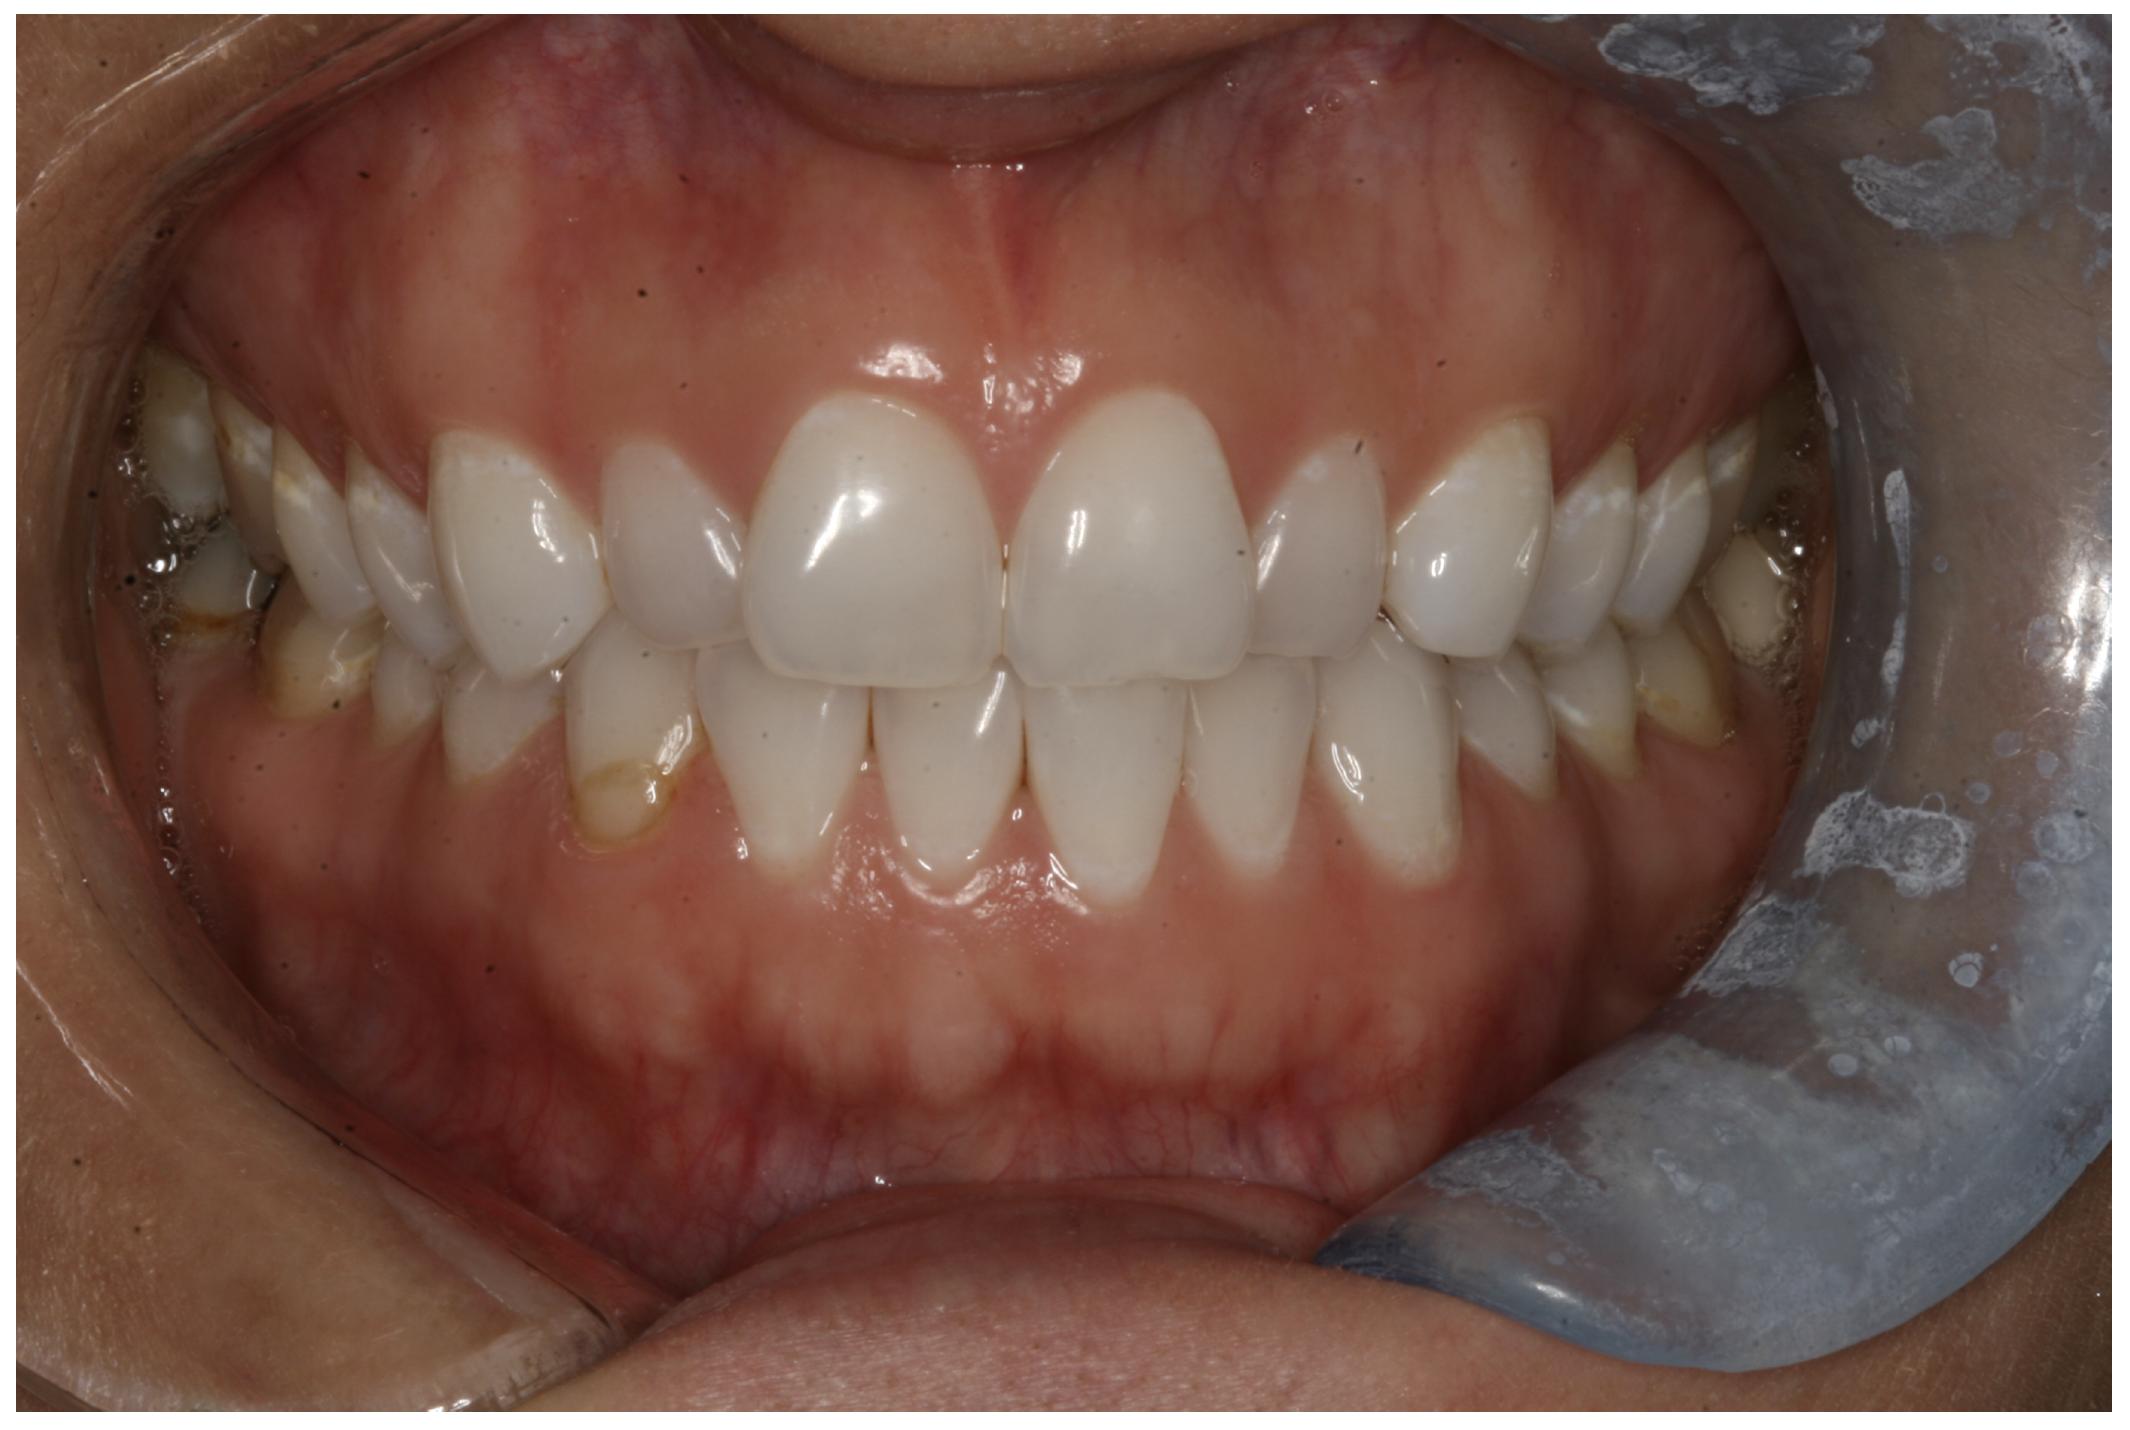

For the case in Figure 9 through Figure 11, the patent presented for an initial consultation with bonding completed on teeth Nos. 7 through 10 a few years prior with a chief complaint of not liking the way the resin bonding looked and how it was wearing. Up to this point, the bonding had repeatedly chipped and been repaired three times already. The patient's canines also exhibited signs of incised wear and flattening, which she did not like. Based on the patient's goals for her smile and her financial budget, she elected to have porcelain veneers completed on teeth Nos. 6 through 11. The total esthetics of the case design were somewhat limited given that the patient's esthetic zone included her posterior teeth and mandibular anterior teeth. Therefore, the color and characteristics of the veneers had to match her existing dentition closely.